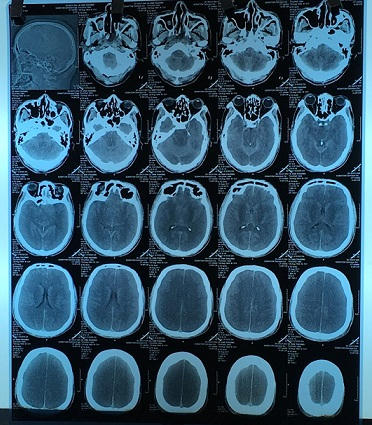

Kết quả chụp phim cho thấy: não bị phù, căng cả 2 bên. Dấu hiệu gợi ý nhu mô não tổn thương nặng và lan rộng cả 2 bên. Nồng độ methanol trong máu là 210 mg/dL (gấp nhiều lần so với nồng độ gây tử vong, khoảng 40-50 mg/dL đã là rất nặng).